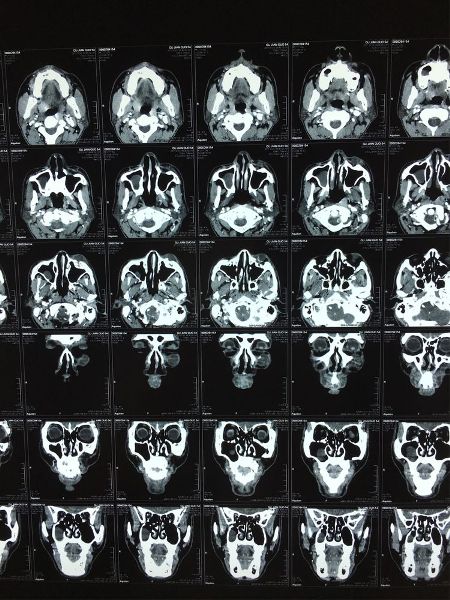

鼻窦CT

螺旋CT